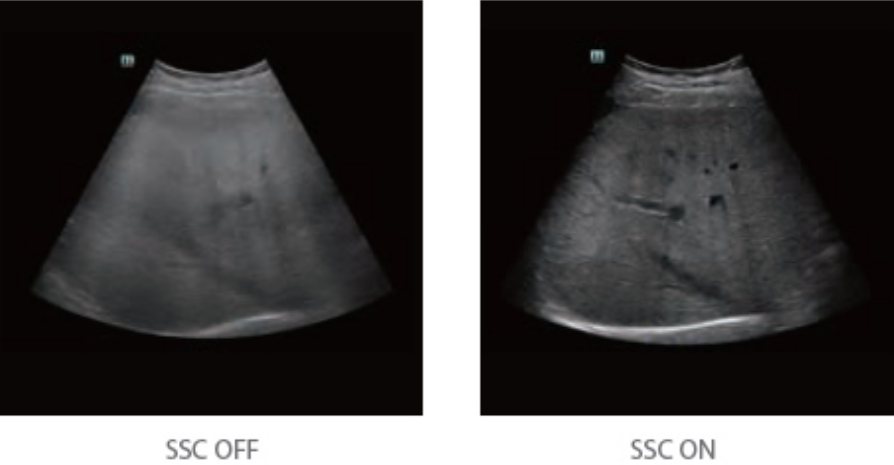

By retrospectively analyzing complete channel data stored in channel data memory, the Resona 6 is able to intelligently choose the optimal sound speed to improve image accuracy even with tissue variation, allowing for adaptive tissue-specific optimization.